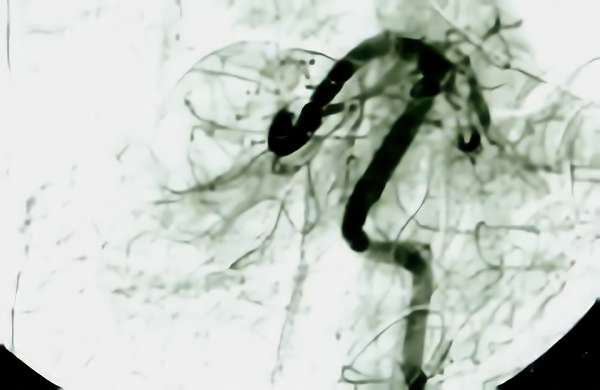

脳血管撮影

手術前

手術後